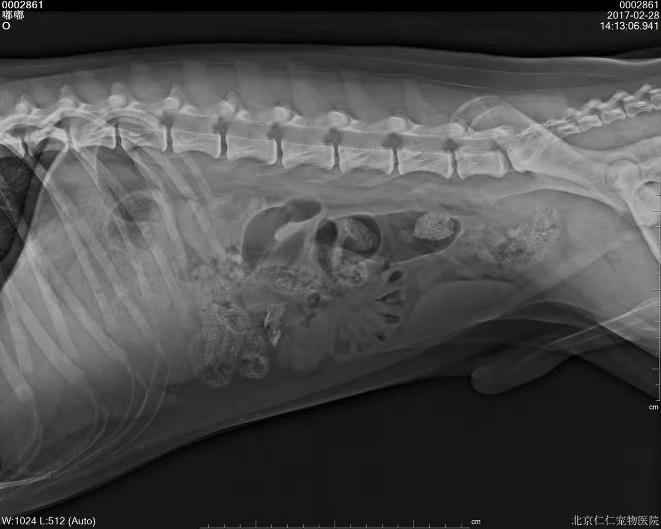

b. X射线检查:对于阻线性较强的物质(如金属、骨头)较容易辨别,对于阻线性与组织密度相似的物体较难确定,但是能够通过消化道灌服造影剂判断是否有阻塞或可包裹物体。

胃的正常大小:胃位于前腹部,隔和胆脏之后。胃排空时位于肋弓以内;从腹底算起,胃的腹侧缘大约在腹腔深度的1/3处。胃充盈时,胃向后向下延伸,与横结肠和腹底部相接。

胃内异物(金毛,手术取出6cm大衣扣子)

钡餐4小时后胃内未排空(家猫,线性异物)

c.X线检查。对于阻线性较强的物质(如金属、骨头)较容易辨别,对于阻线性与组织密度相似的物体较难确定,但是能够通过消化道灌服造影剂判断是否有阻塞或可包裹物体。

机械性肠梗阻的读片要点:1.体积增大;2.形态轮廓变化;3.影像密度变化;4.浆膜细节变化。

金毛 线性异物